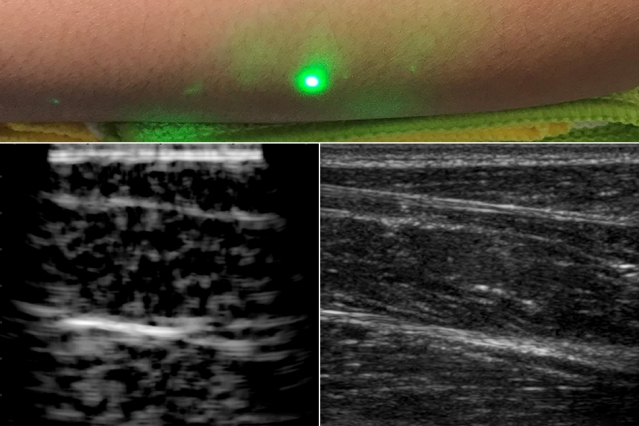

Научници развија систем на ласери кој може да го испитува човечкото тело, приближно како ултразвук, но од далечина.

Системот опишан во истражувањето објавено во списанието „Лајт: Сајенс енд апликејшнс“ користи два ласера: еден за генерирање звучни бранови кои отскокнуваат во телото на пациентот и вториот за нивно детектирање додека се одбиваат.

Крајните резултати не се точни како оние генерирани од традиционален ултразвук, но фактот дека ласерски систем може да гледа во тело на лице од далечина без да му ја изгори кожата или очите е огромен чекор напред за неинвазивните медицински процедури.